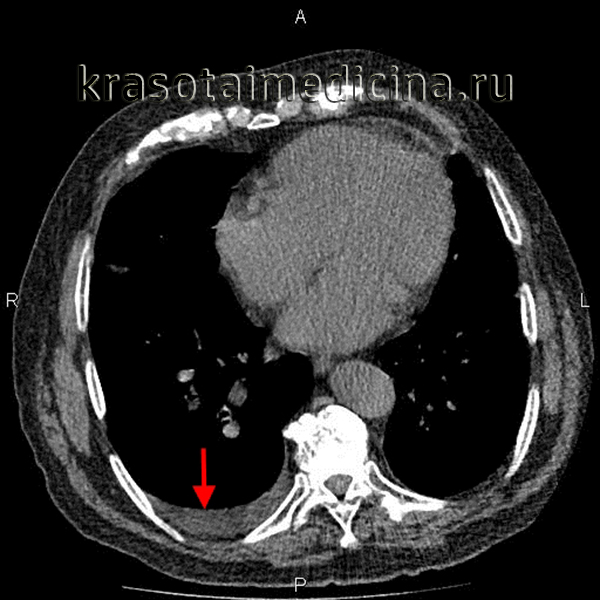

Осумкованный плеврит – локальное скопление экссудата, ограниченное плевральными сращениями от остальной плевральной полости. В зависимости от локализации и объема экссудата клиническая картина варьирует от бессимптомного течения до выраженных проявлений, включающих боли в грудной клетке, одышку, кашель, затруднение глотания. Диагноз осумкованного плеврита выставляется на основании результатов рентгенографии легких, КТ грудной клетки, УЗИ плевральной полости, торакоцентеза. Лечение осумкованного плеврита зависит от его этиологии, которая устанавливается после исследования экссудата (антибиотикотерапия, противотуберкулезная терапия, по показаниям – хирургическое вмешательство).

С учетом этиологии различают парапневмонические, туберкулезные, панкреатогенные, опухолевые, посттравматические, ревматические осумкованные плевриты. На основании локализационного критерия и клинико-рентгенологической картины в пульмонологии выделяют следующие виды осумкованного плеврита:

- паракостальный (пристеночный) – уровень жидкости своим широким основанием прилежит к реберной поверхности;

Для первичного выявления осумкованного плеврита чрезвычайно важны данные полипозиционой рентгенографии грудной клетки (в прямой, боковых и косых проекциях) и рентгеноскопии легких. Рентгенологически осумкование проявляется в виде затемнения характерной локализации и формы. В сложных случаях для дифференциальной диагностики требуется наложении искусственного пневмоторакса и пневмоперитонеума, проведение КТ легких. Длительное существование осумкованного плеврита может отразиться на состоянии легочной паренхимы. Поэтому для оценки изменений прилежащих отделов легкого (бронхов, сосудов) используются рентгеноконтрастные исследования - бронхография и ангиопульмонография.

УЗИ плевральной полости позволяет оценить объем и предположительно характер экссудата, выбрать оптимальный доступ для его эвакуации. Плевральная пункция с визуальной оценкой и лабораторным анализом плевральной жидкости в большинстве случаев ставит точку в определении этиологии осумкованного плеврита. В ряде случаев для установления этиологического диагноза требуется проведение диагностической торакоскопии с биопсией плевры.